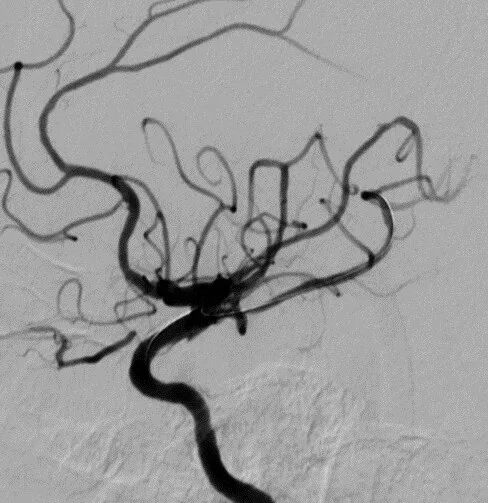

全脑及病变处不同体位造影。

导丝怎么扩【载药时代 球扩天下】NOVA DES®颅内药物洗脱支架在颈内动脉颅内段重度狭窄中的应用体会二例!_https://www.jmylbn.com_新闻资讯_第13张

导丝怎么扩【载药时代 球扩天下】NOVA DES®颅内药物洗脱支架在颈内动脉颅内段重度狭窄中的应用体会二例!_https://www.jmylbn.com_新闻资讯_第14张